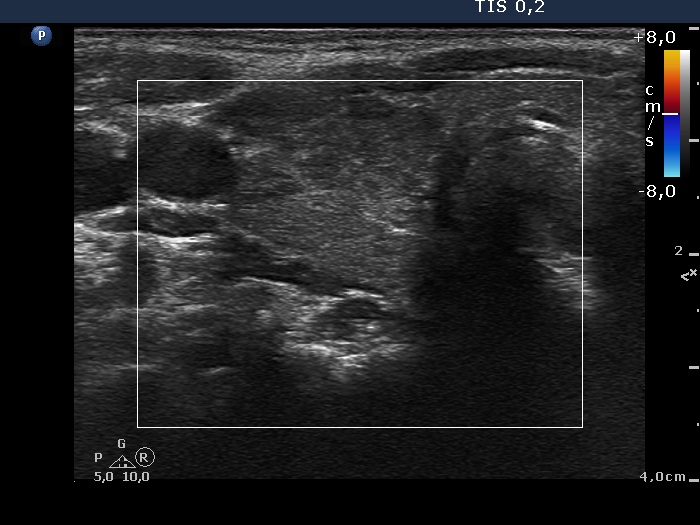

First examination (first and second rows of images):

Clinical presentation: A 33-year-old woman was referred for an evaluation of complaints suggesting hyperthyroidism. The patient was never pregnant.

Palpation: no abnormality.

Results of blood test: TSH undetectable, FT4 31.0 pM/L, aTPO 703 U/mL, TSAb 0.5 U/L (normal value < 1.5).

Ultrasonography: A diffusely hypoechogenic thyroid was found with several discrete lesions. The vascularization was increased.

Cytology was performed from the right lobe.Cytological diagnosis: benign pattern corresponding to hyperthyroidism without any signs of thyroiditis.

Considering the results of investigation, low dose (daily 15 mg) methimazole was administered.